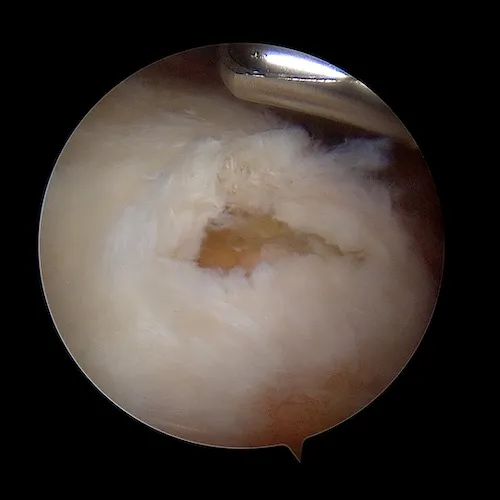

La rupture tendineuse est visualisée dans l'espace bursal sous la forme d'un "trou" dans le tendon. Les fibres tendineuses parthologiques sont réséquées afin de ne garder que du tendon sain. C'est ce tendon qui va être ensuite réinséré sur l'os.

La surface osseuse est ensuite préparée. L'os est avivé grâce à une fraise motorisée. Ce geste permet la revascularisation du tendon réinséré et la cicatrisation sur l'os.